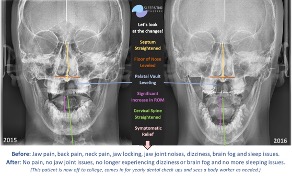

Results After One Year of Treatment